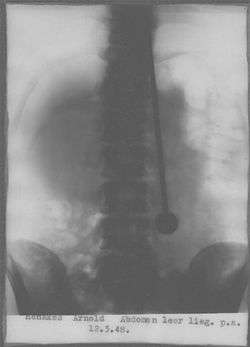

He was allegedly instructed by voices to eat a steel needle which was to be surgically removed. He did so on May 11, 1948. It was surgically removed on May 13, 1948. During recovery in the hospital he requested a lot of water for recovery which was only granted if he took full responsibility. To demonstrate his health he walked through Zurich directly after being released. Ten days later, when De Groot picked up his wife from the airport, Dajo lay down on a bed and went into a trance-like state. On arrival De Groot's wife was not comfortable with someone lying down as if dead, and asked De Groot to check his health. On the third day De Groot's wife asked him to check again. This time his neck felt cold.[4] The medical examiner announced he had been dead for a day. The autopsy revealed Dajo had died of an aortic rupture, though this was contested by De Groot and the aforementioned surgeon.[1]